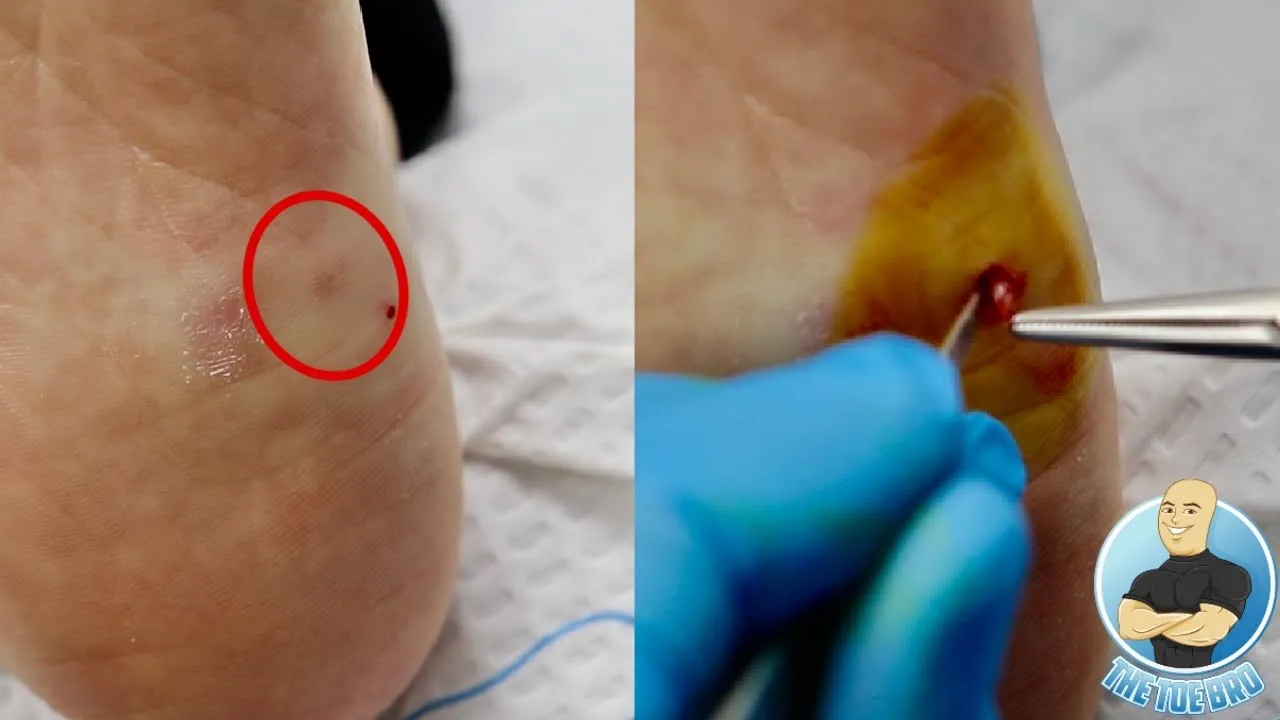

Infected blister gets popped!!! ***what's underneath?!***

February 20, 2021

Ingrown Removal